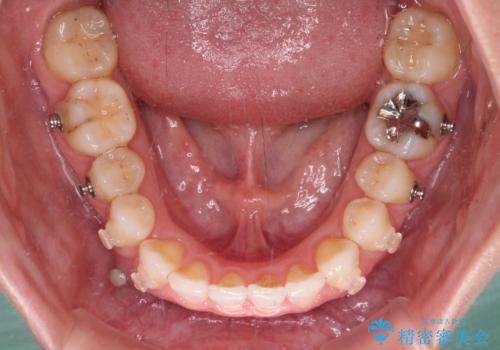

インビザラインは長時間装着を自己管理する必要がありますが、残念ながら十分な時間の装着を行うことができませんでした。

何とか矮小歯を改善するスペースを作ることはできましたが、過蓋咬合を改善するには至りませんでした。